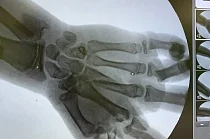

В покой медицинского учреждения юный пациент поступил в шоковом состоянии. Врачи констатировали у него перелом нижней трети левого предплечья со смещением, раны левой голени и лба, но самым опасным стало травмирование левой кисти. Взрыв спровоцировал в ней множественные переломы костей и сильнейшее кровотечение, риск потери части конечности был весьма высок.

Вмешательство длилось полтора часа. За это время врачам удалось остановить кровотечение сосудов, предотвратить распространение инфекции и выполнить такую сложную задачу, как установка и адаптация костных обломком кисти относительно друг друга. Одним из ключевых моментов операции стало обеспечение кровотока в пострадавшей конечности.

«Поэтому чтобы правильно выстроить дальнейшую стратегию лечения, необходимо было выждать время, – объяснил Александр Гозун. – В итоге через несколько суток, оценив зону некроза, которая благодаря вовремя обеспеченному кровотоку в кисти оказалась небольшой, мы провели мальчику вторую, восстановительную операцию. Во время нее с помощью пластики были устранены дефекты тканей и кости».